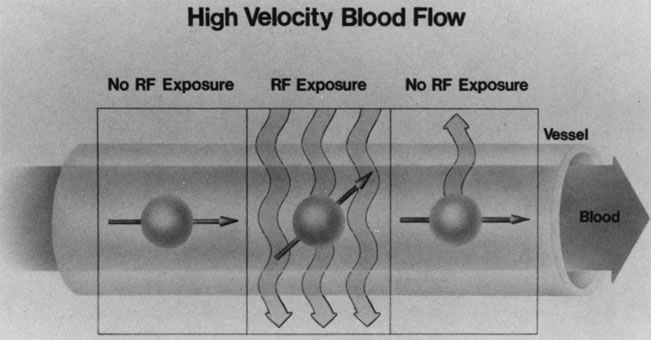

FLOW OF PROTONS

Blood vessels with rapidly flowing blood usually appear as regions of low intensity in contrast to the surrounding tissues. This phenomenon is explained by the fact that excited protons in the blood within the imaging slice that received the RF pulse pass outside the slice before their signal is detected by the RF receiver coils (Fig. 10). By the time the slice is imaged, the replacement blood, which has not received the RF energy stimulus, does not yield a signal, and consequently the blood vessel appears dark.5,17